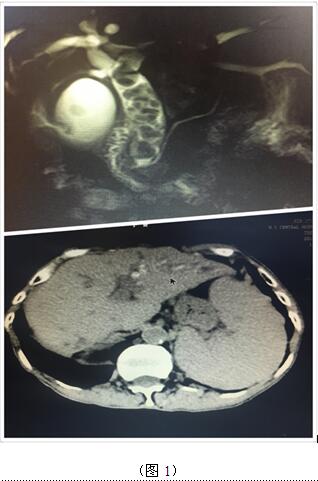

70歲高齡的曹奶奶是一個(gè)膽內(nèi)膽管結(jié)石、膽總管結(jié)石、膽囊結(jié)石的高齡患者,由于結(jié)石部位多發(fā)(圖1),當(dāng)?shù)蒯t(yī)院多次住院治療,均建議開(kāi)大刀切除部分肝臟;同樣患肝臟腫瘤的張爺爺,由于腫瘤位于肝臟尾葉,而且壓迫腹腔大血管(圖2),尋遍多家醫(yī)院都只能開(kāi)腹手術(shù)切除,聽(tīng)說(shuō)衡陽(yáng)市中心醫(yī)院腹腔鏡手術(shù)技術(shù)成熟遂慕名而來(lái)。肝膽外科周玖橋主任和李鑫副主任醫(yī)師仔細(xì)分析病情后決定為倆位患者行3D腹腔鏡手術(shù)。